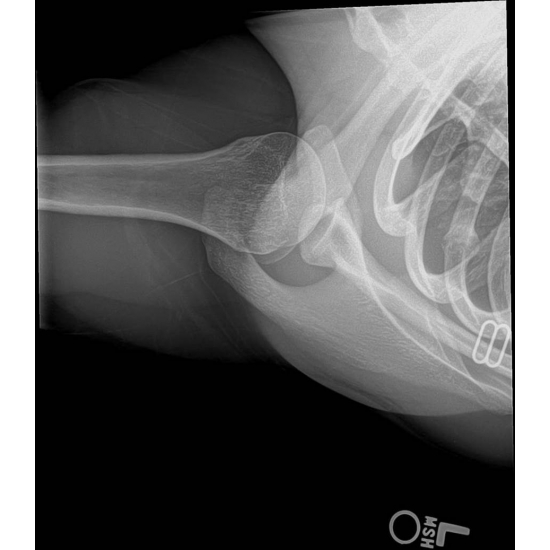

| Too Much Pain, No Gain: Rib Stress Fracture In A Cross Fit Athlete - Page #3 | |||